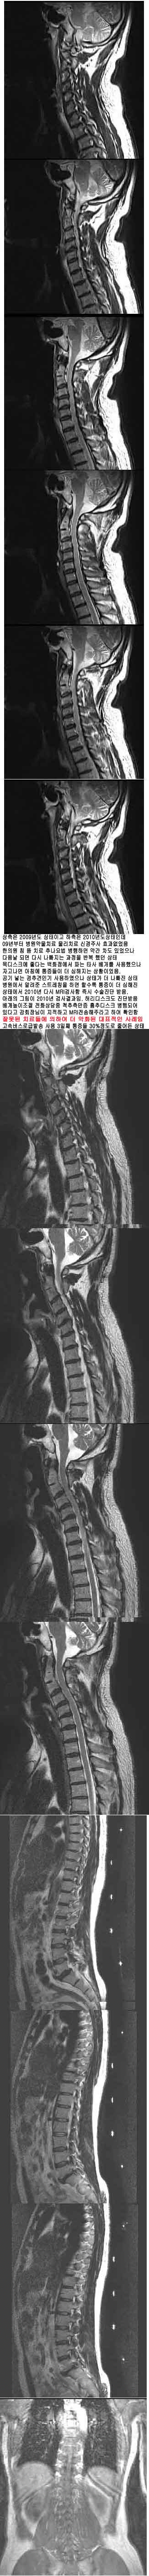

̷ ġ ¿ ȭǰ ־ ؾѴٴ *#ö@& mri ȸ Դϴ. 2009 * ̰ 2010 ε 09 ġ ġ Űֻ ȿ ǿ ħ ġ ߳ ϸ ణ ־ Ǹ ٽ ݺ ߴ ũ ٴ ȭ Ĵ Ÿ ڰ ħ Ȳ̾. ִ ߰α Ͽ ° ͳݰ ġ ǻ簡 ˷ ٴ ƮĪ ϸ Ҽ ¿ 2010 ٽ MRI˻ . Ʒ 2010 ˻. 㸮ũ ܹ ȭ ô ߵũ Ǿ ִٰ ȸ ϰ MRIֶ Ͽ Ȯ ߸ ġ鿡 Ͽ ȭ ǥ ӹα 3° 30% پ [ֹȣ : 20100921132830y04140] * ֹ ֹϽ : 2010-09-21 13:28:30 +ְ 160ȣ ǥغ 160-210ȣ γ,ûҳ Ű 168 71 54 ˰Ե ͳ ˻ڷ õ ǥغ ϱ ȣϽ 1C.ٺҸ, 1C.ٸǷ 1C.ھ 1C.ټ Ǹ 1C.ٱ () 1C.߷ () 1C.Ƿ () 1C.̸, 1C.ڱ ֺ ̻, 2C.ھȱ, 2C.ڴ, ýŰ , 2C.ڽ÷ 2C.ھȱ, 2C.ڴ 2C.ٴ, 2C. . 2C.ڹ̰̻ 3C.ġ Ű 4C. ֺ 5C.ٸ, 6C.ڸ 6C.ھ Ḳ 6C.ڻ 6C.7C.ھ հ ̳ 7C.Ȳġ 7C. 1T.ڼո 1T.Ȳġ 5T. 6T.ڼȭҷ 7T. 10T.ٸǷ 4L.° 4L. 财, 4L. ϴ 财 5L.ڹ߹ٴ̳ ߵ ̳ ȭŸ̳ 5L.Ƹ 㰡 (). ()ũ( ߰Ż) źϸ Ը ũ(߰Ż), ũ(߰Ż)ġ, հ , , հ , ġ, , Ḳ , , Ḳ ġ ȱ ǰϰų 㸮ũ(߰Ż) ߿ ġ Ƿ ġ 索ġ γ Ȱ ǥغ ϰ ߴ ġ ǿ ġ ħ ġ αġ ī̷ƽ ߳ ġ غ ϴ ġ ϴٰ ȭDZ 2009 8 ù mri˻系. ߵٰ 3 ȭǰ ؾѴٰ ܹ ᵵ ڰ ϻȰ ---------------------------------------------------------------------------------- 21 ֹϼ̰ 22 ӹ ù 80л 3/10 پ · Ϸڰ 23 Ľð 111 1.5/10 پ· Ͽ Ѻ Ʈ 926 ߰˳Դϴ. Ҹ,- ֹŴϴ. ̸, ֺ ̻,- ʹ Ÿ ʾҴϴ. ȱ, , ýŰ , ȱ, ó ſ ִٰ ϴ. . ̰̻- ϴ. Ư ġῡ ˾ ƹ ִϴ. ġῡ ȣ ڲ ߵǴ Ȳ ̷ ȿ Ÿϴ. ,- µ ǥغ Ÿ ʾҴϴ. , -- ǥغ ƴ϶ϴ. Ḳ Ȳġ پ پ ִ ȲԴϴ. ո , Ȳġ-- ȣ ʴϴ. ȭҷ-- ȭ ߵȴϴ. -- 350̴ 2 270 · °, 财, ϴ 财--ٱⰡ 絵 ÿ 㿡 Һ ¶ϴ. ߹ٴ̳ ߵ ̳ ȭŸ̳ , Ƹ 㳪° Ÿ ʾ ø ִϴ. : 21 ֹϼ̰ 22 ӹ ù 80л 3/10 پ · 2010-09-24 14:20:51 Ȩ : Ϸڰ 23 Ľð 111 1.5/10 پ· Ͽ Ѻ 2010-09-24 14:21:07 Ȩ : а ־ Ѵٰ ڸ Ǿ ȸԲ 24 120 ȭϰ پ ٽ 2010-09-25 11:29:06 : ȯںв ε Һ ͵ . ̰ ̻ ˾ ġ ʾҴµ ƹ ִٰ Ͻ. ̺İ 6 ġ ġῡ ڲٸߵǰ . ?/TD> 2010-09-26 12:43:00 : Һٱ , ̻, ó ġῡ ʾҴ 4 ٰ 2010-09-26 12:44:48 : 索 ġ 350̴ 2ϸ ħ 270 . 2010-09-26 12:46:43 2002 10 28 ߰ ˳Դϴ. ƿ е о Ϻʹ ġ ġ ߱ ƮĪ ٽ ϰ ġ ϱ |